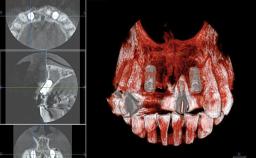

Replacement of Four Incisors with a Fixed Partial Denture on Two Narrow-Neck Implants after Implant Failure

| Bone Volume | Deficient vertically or deficient vertically AND horizontally |

| Anatomic Risk | High |

| Esthetic Risk | High |

| Complexity | High |

| Risk of Complications | High |